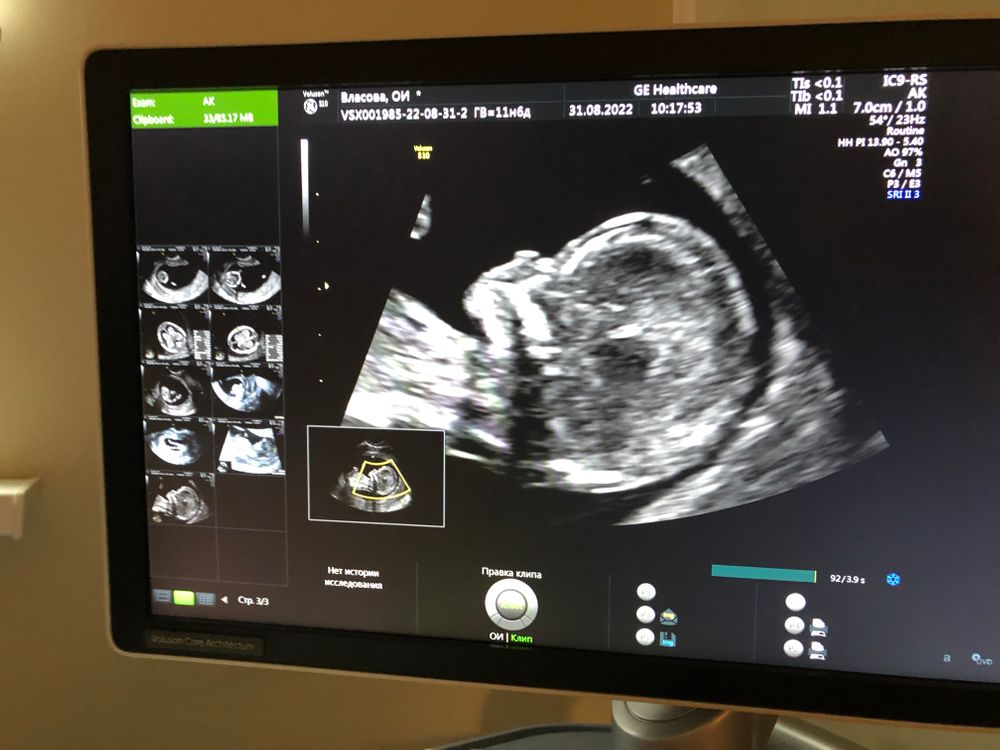

Первый скрининг

Ой девочки, сегодня мы с мужем ходили на встречу с нашим малышом.

Все показатели хорошие, все органы, конечности, части тела, сосуды, воротниковое пространство и т.д. идеальны, как доктор говорила, но есть одно но, малыш не дал измерить нормально нос. Он лежал полубоком, и только часть носа могли измерить, а полностью не удалось. Что я только не делала, приседала, ходила по коридору, ела шоколадку, и так мы делали 3 перерыва, чтобы ребенок повернулся так как нам надо, но у него другие планы. 1 раз уснул, 1 раз повернулся спиной, ноооо ровно не лег. Поэтому 6 сентября я иду на повторное узи, чтобы измерить нос, и обязательно мне нужно поесть. Мне доктор сказала, что очень плохо, что я не поела.

А еще наш малыш на неделю опережает показатели.